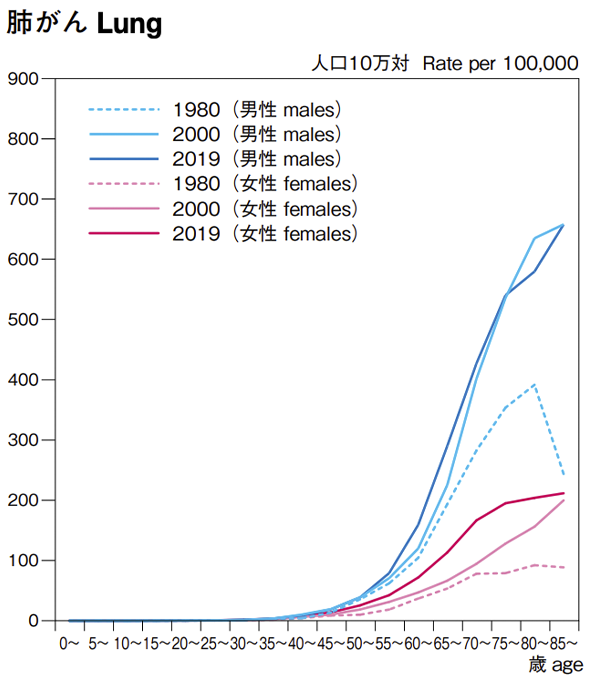

肺がんの中でも、年齢が上がるほど罹患者数が増える傾向は明らかです1)。下表は、肺がんの罹患率(人口10万人に対する肺がん患者さんの割合)を男女、年齢層別にみたものです。男女ともに、特に70歳以上で増加していることがわかります。

また、全体的に女性よりも男性のほうが、1980年以降の罹患率の伸びが顕著です。

年齢階級別 がん罹患率推移(1980年、2000年、2018年)